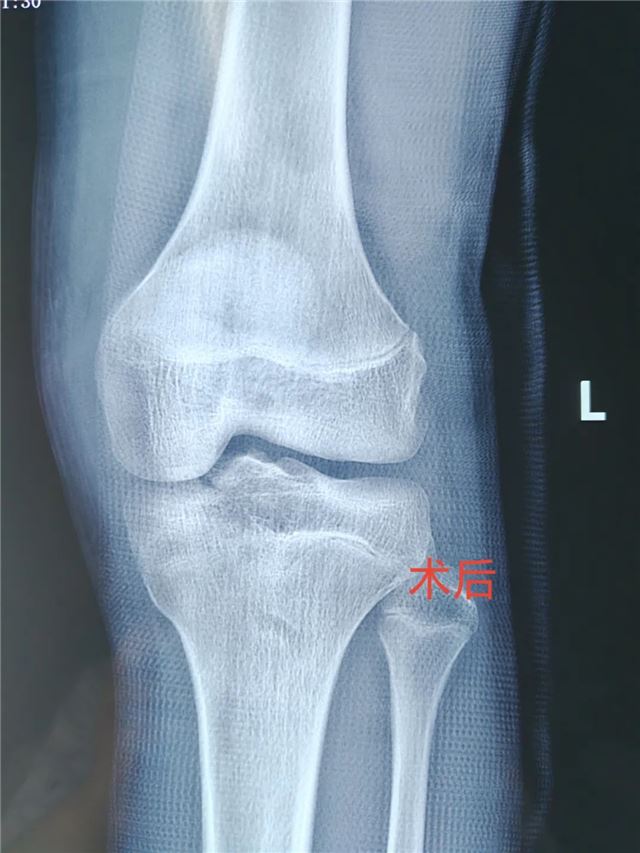

近日 长治二院小儿骨科团队 成功完成首例 关节镜下胫骨髁间棘骨折复位固定手术 标志着 长治二院小儿骨科 在青少年运动损伤及关节 微创治疗领域又上新台阶! 术前 术中 该手术通过仅0.5cm的微小切口,结合高清关节镜技术,实现骨折精准复位与牢固固定,术后患者无疼痛、恢复快,早期可下地活动,为青少年患者提供了更优治疗方案。 技术亮点 创伤极小:避免传统开放手术的大切口,减少软组织损伤。 精准高效:关节镜高清视野助力精准复位,固定牢靠。 康复迅速:术后早期功能锻炼,缩短住院时间,降低并发症风险。 美观无忧:微创切口隐蔽,术后疤痕几乎不可见。 适应人群 运动损伤致胫骨髁间棘骨折患者。 膝关节外伤后疼痛、活动受限者。 追求微创、快速康复的青少年患者。 咨询电话: 主任医师任泽恩:13008078999 周一、周五、周六上午专家门诊 主治医师牛佳伟 18834181790 周日上午节假日门诊 科普园地 01 胫骨髁间棘骨折是什么? 胫骨髁间棘是膝关节内交叉韧带附着的重要结构,骨折多由运动损伤(如急停、扭转)或高能量外伤(如车祸)导致,表现为膝关节剧痛、肿胀、无法伸直,易误诊为韧带损伤。 02 传统手术 vs 关节镜微创手术 传统开放手术:需切开关节囊,创伤大、恢复慢,可能遗留关节僵硬。 关节镜手术:通过2-3个5mm小孔完成,镜下精准复位骨折块,配合可吸收螺钉或缝线固定,最大程度保护关节功能,术后可早期开始康复锻炼。 03 术后康复小贴士 早期冰敷+踝泵训练,减轻肿胀 术后2周内拄拐部分负重,逐步过渡到全负重 4-6周后结合理疗加强膝关节活动度与肌力 微创技术,让运动之痛不再成为人生绊脚石!长治二院小儿骨科将持续深耕关节微创领域,以尖端技术守护儿童“膝”望! 名医推荐 任泽恩 主任医师、教授 骨科党支部书记 小儿骨科病区主任 硕士研究生导师 牛佳伟 主治医师 骨科学硕士 【专业特长】 儿童创伤保守和手术的微创治疗。四肢畸形矫正(先天性或创造成的肢体内外翻、肢体不等长等)。手足部多指/趾畸形、并指/趾畸形等。曾于北京参加“骨外固定与肢体重建基础实战技术培训班”。 科室简介 小儿骨科于2019年创立,现病床配置18张,科室现有主任医师1名,副主任医师1名,主治医师1名,住院医师1名,其中硕士研究生2名,硕士研究生导师1名,目前是长治地区唯一专业诊治儿童骨骼疾病的专业科室,年门诊量5000余人次,年手术近500例。 科室成立5年来,我们小儿骨科团队同心协力,追求卓越,推动学科快速发展。我们小儿骨科开展的多项手术技术处于省内领先地位,辐射影响达周边地市,在上党地区享有盛誉,得到了国内、省内业内同行及患者家属的高度认可。目前以京长合作为契机积极与北京积水潭医院小儿骨科紧密合作,成立了“吕学敏教授团队名医工作室”,定期派专家来我院坐诊、讲学、查房,开展新技术新项目、疑难病例会诊及手术指导。大大提高了诊疗疑难疾病的能力。 诊疗范围:14周岁以下的儿童骨病患者(含14周岁)。目前已经开展的技术项目:小儿四肢关节创伤微创手术治疗、部分小儿先天性及发育性畸形矫正、四肢与关节特异性及非特异性炎症、儿童各类软组织疾患及骨肿瘤。(肱骨髁上骨折闭合复位经皮克氏针内固定、儿童四肢骨干骨折弹性髓内针内固定、青少年股骨干骨折交锁髓内钉内固定、肘关节关节内骨折手术治疗、手足多指(趾)畸形切除及矫形术)。 编 辑丨翟艳鹏 初审初校丨牛佳伟 复审复校丨任泽恩 终审终校丨雷 赫